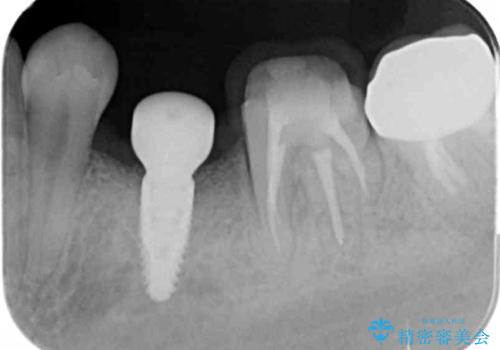

- 残していた乳歯がぐらつき始め、抜去ののちのインプラント治療を希望され来院されました。

乳歯を抜去して歯ぐきの状態が落ち着いたのち、骨の増成を伴うインプラント治療を行い機能の回復を図ります。

生まれつき永久歯の欠損がある場合、乳歯が大人になっても残っている場合があります。

残念ながらぐらつきが大きくなり、残すことが難しくなり抜去したのちインプラントを用いて咬合機能の回復をしっかりと行いました。